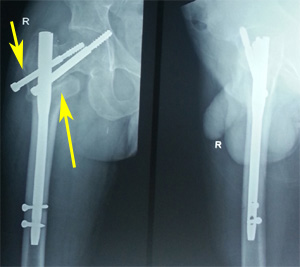

Figure 5b Post-operative radiograph showing varus mal-reduction (pointed by thin arrow as medial overlap of fragments). Also note the superior position of the screws (thick arrow).

Figure 5c Six weeks post-operative radiograph showing varus collapse (thin arrow), cut-out (thick arrow) and fixation failure.